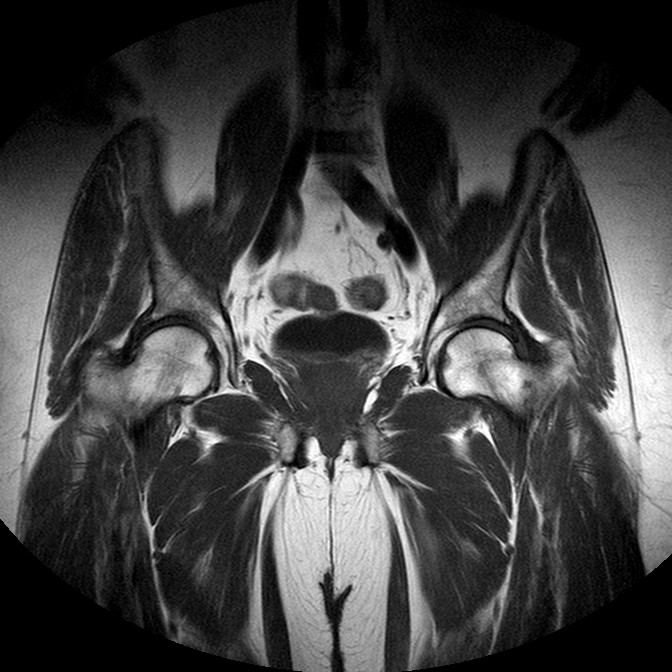

Esami: RMN BACINO

T1w TSE

Evidenti e simmetriche alterazioni osteofitosiche in regione coxo femorale con riduzione delle rime articolari. Degenerazione completa del cercine glenoideo. Non attuali segni di versamento articolare. Non segni di edema osseo che escludono attuale algodistrofia od osteonecrosi. Lieve e simmetrica riduzione del trofismo della muscolatura glutea.